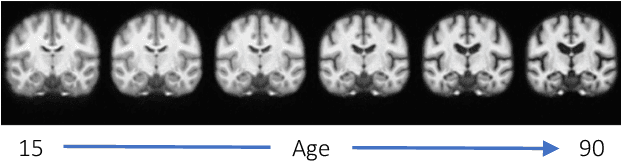

Abstract:Deformable templates, or atlases, are images that represent a prototypical anatomy for a population, and are often enhanced with probabilistic anatomical label maps. They are commonly used in medical image analysis for population studies and computational anatomy tasks such as registration and segmentation. Because developing a template is a computationally expensive process, relatively few templates are available. As a result, analysis is often conducted with sub-optimal templates that are not truly representative of the study population, especially when there are large variations within this population. We propose a machine learning framework that uses convolutional registration neural networks to efficiently learn a function that outputs templates conditioned on subject-specific attributes, such as age and sex. We also leverage segmentations, when available, to produce anatomical segmentation maps for the resulting templates. The learned network can also be used to register subject images to the templates. We demonstrate our method on a compilation of 3D brain MRI datasets, and show that it can learn high-quality templates that are representative of populations. We find that annotated conditional templates enable better registration than their unlabeled unconditional counterparts, and outperform other templates construction methods.